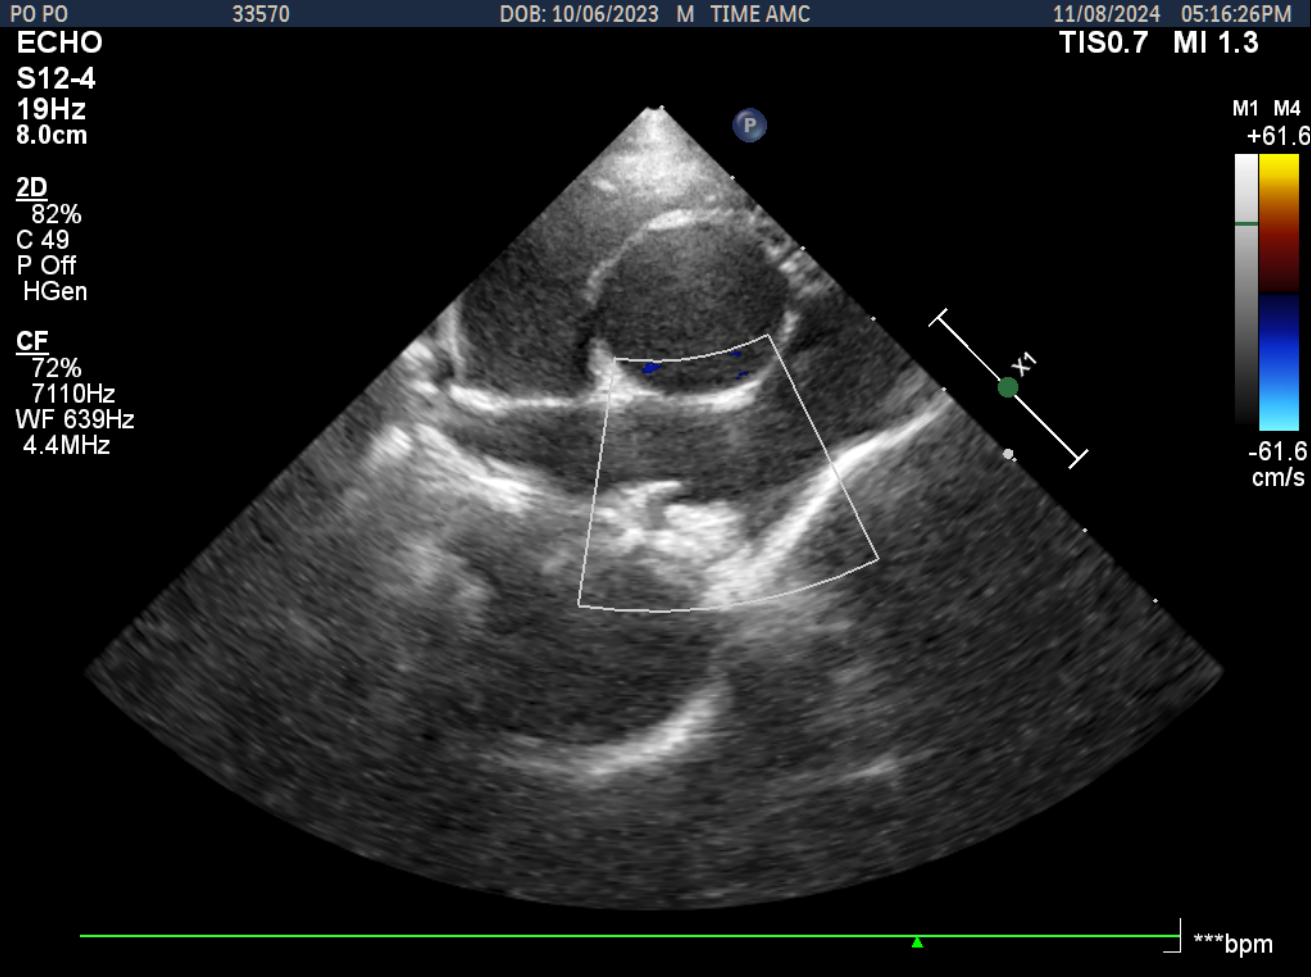

PDA 교정 시술 전후 초음파 비교

시술 후 1

시술 후 2

PDA 교정 시술 전후의 초음파 비교입니다. 시술 전에는 동맥관 개존증으로 인한 비정상적인 혈류 패턴이 도플러 초음파로 확인되며, 시술 후에는 PDA plug 삽입으로 정상적인 혈류 패턴으로 회복된 상태를 보여줍니다.